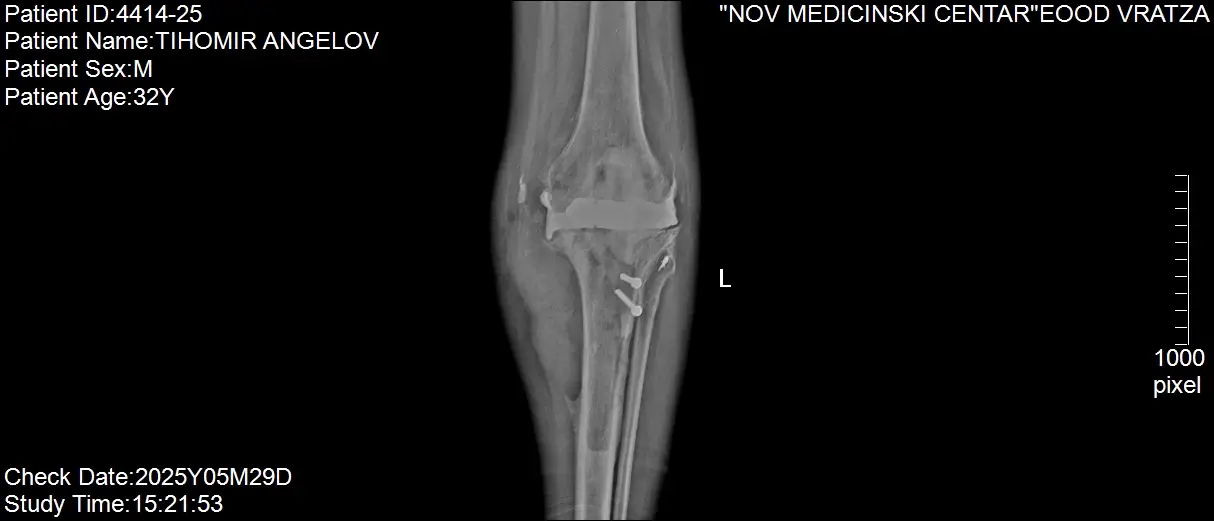

Здравейте, След претърпяно пътно транспортно произшествие на 08.02.2019 г. ми е направена операция на лява колянна става, с поставяне на външен фиксатор;

На 21.02.2019 г. и 13.03.2019 г. са направени 2 ортопедични операции с плавно възстановяване на ляво коляно; През месец Декември2023 г. e извършено ендопротезиране на лява колянна става. Една година след ендопротезирането получих инфекция в областта на коляното с незарастваща отворена рана.

Следва лечение в Ортопедично отделение ИСУЛ, където ми е поставен спейсър - антибиотична става. От 15.10.2024 г. до 17.12.2024 г. съм лекуван в Отделение по пластична хирургия в „Пирогов“, където е взета мускулна група от ахилеса и е добавена към коляното за да се затвори раната - изписан съм с подобрение. На 17.03.2025 г. съм диагностициран с хроничен остеомиелит.

Антибиотичната става не е постоянна и до сега трябваше да бъде заменена с постоянна такава, както и да бъде проведено лечение на инфекцията, тъй като ако същата не бъде спряна, съществува голям риск от ампутация на крака. Поради пластичната операция върху коляното и хроничния остеомиелит, клиниките в България отказват лечение и ново ендопротезиране.